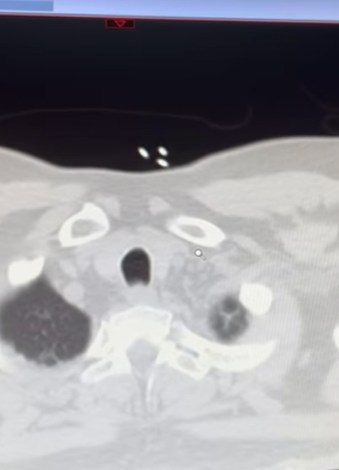

On January 14, 2023, Lalit Modi took to his Instagram handle and shared a series of pictures featuring his multiple selfies and screengrabs of his medical reports. He also shared a picture of a fingertip pulse oximeter in which we can see the reading 87, which clearly shows how seriously low was his oxygen levels. Along with the pictures, Lalit Modi also penned a long note in the caption. In his note, he thanked his son, Ruchir Modi, for arranging everything to bring him back to London. His note can be read as: